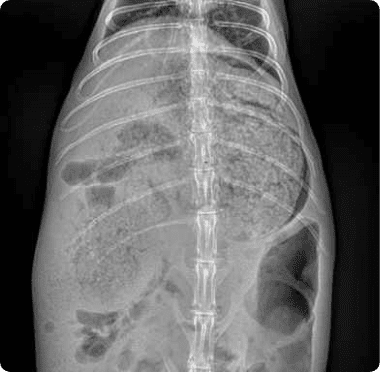

피부질환, wet tail 같은 소화기 문제의 내과질환부터

햄스터 자궁축농증 수술, 종괴제거 수술, 알막힘 등 다양한 질환을 치료합니다.